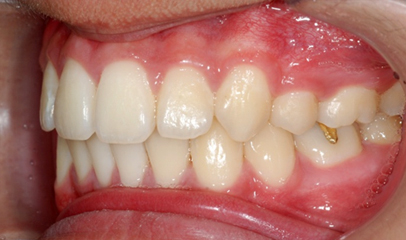

발치 돌출입 교정

전후 사례

발치 교정, 치료기간 약 2년

Before

After